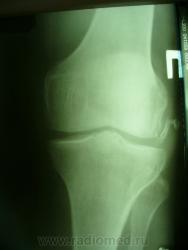

Уважаемые коллеги. Не так давно на странице сайта обсуждалась тема гипердиагностики ДОА. Хотелось бы увидеть ваше мнение по поводу наличия/отсутствия ДОА на представленных снимках. Лет 8 назад попал в автодорожку где-то в другом регионе, там же лечился в НИИТО (со слов, т.к. документов никаких нет) и там же наблюдался с DS: ДОА правого к/с IIст. Переехал в наш регион и решил пройти МСЭК для получения группы инвалидности. Снимки перевернуты, чтобы скрыть маркировку. Так есть ли ДОА?

Есть. Но 1 й ст. обоих к.с.

Едва заметное сужение суставной щели только в левом к/с. На каком основании ДОА?

На мой взгляд - "норма".

Латерализация обоих надколенников, мелкий остеофит по верхнему краю правого надколенника, вытянутость и заострение межмыщелковых отростков левой б/б кости.

Прямая проекция сделана одним лучем на одной пленке, это я их "разделил". Может, из-за этого латерализация? Остеофит левого надколенника есть, никуда не денешься, но ставят артроз (обезображивающий по Рейнбергу) справа.

Вот что хотелось бы уточнить---а что это у нас с межмыщелковыми возвышениями справа???? а что это за окостенение по наружному контуру латерального мыщелка бедра??? ТРАВМА В АНАМНЕЗЕ!!!! Так что - справа - норма? Извините - не уверен. Група не только по снимкам определяется...функция тоже учитывается. А если сделать пару снимков для оценки межмыщелкового углубления и этих самых возвышений.

Выбирай, не выбирай..., а получается только гетерогенное окостенение у внутреннего надмыщелка правой бедренной кости. А с инвалидностью? Косинская как раз и работала в Ленинградском институте экспертизы трудоспособности инвалидов: 2 ст. = 2гр., 3 ст. = 1 гр., в данном случае - никакой группы. Молодцы травматологи, вылечили человека в НИИТОУлыбаюсь!

Все правильно замечено. Это, конечно не пальцы, а дополнительные фрагменты костной структуры. Была травма, больной лечился в ИТО. Вероятно, это окостеневшие фрагменты связок, хряща или чего там еще. И межмыщелковое возвышение "изгрызано", м.б. был перелом верхушек. Но ведь это все это не является R- признаками ДОА. Цель демонстрации - выяснить, есть ли рентгеновcкие признаки обезображивающего остеоартроза?